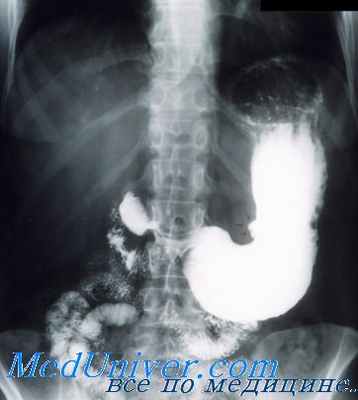

Ниша на контуре обнаруживается при тугом наполнении желудка и представляет собой местное увеличение теней в виде ограниченного выпячивания (рис. 5.8). Ниша на рельефе слизистой имеет вид неправильно округлого стойкого пятна, соответствующего скоплению бариевой взвеси в язвенном дефекте. Выявить ее обычно удается с помощью небольших количеств контрастной массы, т.е. при исследовании рельефа слизистой.

Рис. 5.8. Обзорная рентгенограмма желудка. В средней трети тела желудка на малой кривизне определяется локальное увеличение тени – симптом ниши (стрелка). Язва желудка.

Рис. 5.9. Рентгенография желудка в прямой проекции с контрастированием сульфатом бария. По малой кривизне определяется большая ниша (стрелка) в верхней трети тела желудка с конвергенцией к ней складок слизистой оболочки. Язва желудка.

Инфильтративный вал на контуре виден либо как выступы по краям ниши, либо как сужение входа в нишу.

Инфильтративный вал дает просветление на рельефе (кольцевидное). Конвергенция складок – признак рубцевания (рис. 5.9). Функциональные симптомы: